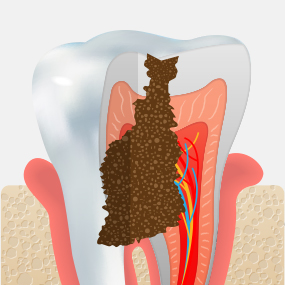

충치가 어느 정도 진행되었는지에 따라 치료 방법은 크게 달라질 수 있습니다. 서울하나치과는 정밀 진단을 통해 치아를 최대한 보존할 수 있는 치료법을 안내해드립니다.

CARIES TREATMENT

상아질 안쪽 신경까지

염증이 진행되어

극심한 통증으로

참기 어려운

정도가 됩니다.